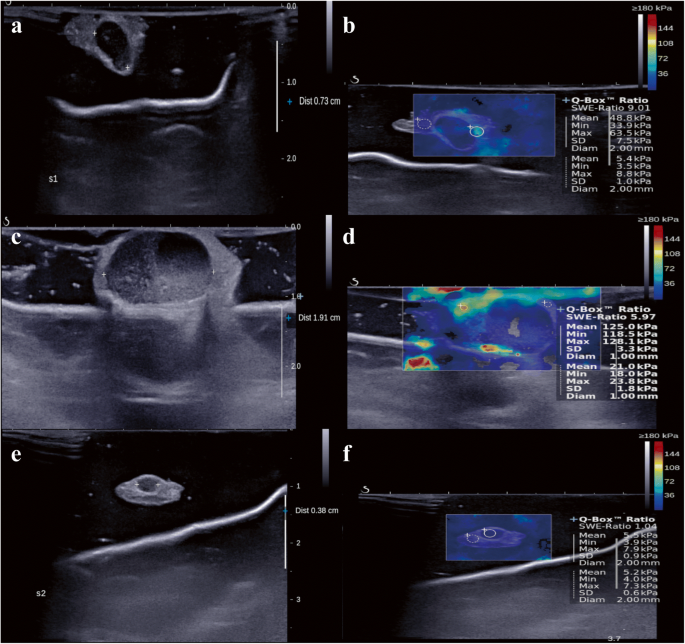

Fig. 1

figure 1

B-Mode ultrasound and shear-wave elastography (SWE). a B-Mode ultrasound showed 0.73-cm–sized excised sentinel lymph node with adjacent fat tissue. b The mean stiffness was measured by placing the 2-mm–sized region-of-interest (ROI) on the stiffest part of the excised sentinel lymph node (circle). The stiffness of the adjacent fat tissue was measured by placing another ROI on the surrounding fat tissue (dotted circle). Then, the elasticity ratio was calculated automatically. ad B-Mode ultrasound and shear-wave elastography (SWE) images of patients with lymph node metastasis. e, f B-Mode ultrasound and shear-wave elastography (SWE) images of patient without lymph node metastasis